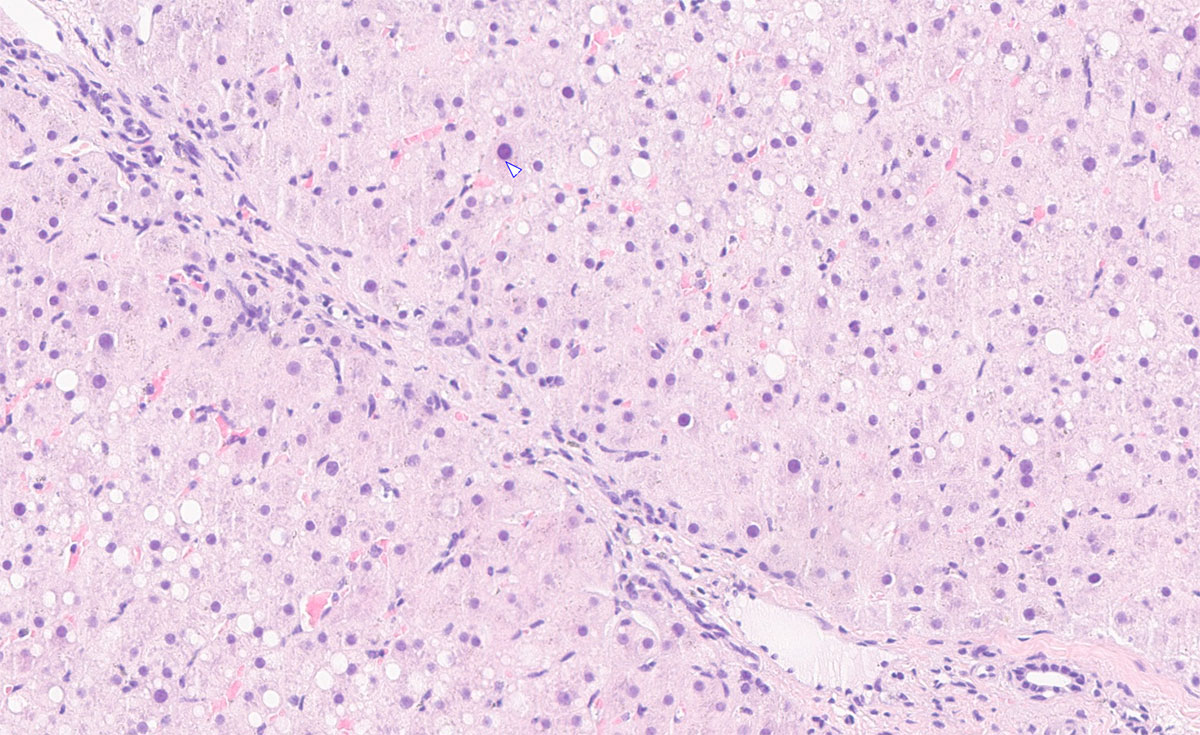

Abb. 1: Leberbiopsie eines Pferdes mit längerfristiger Aufnahme von Mykotoxinen und mutmaßlich Giftpflanzen: gering- bis mittelgradige Fibrose.

Bildquelle: Laboklin

Die labordiagnostische Abklärung von Lebererkrankungen beim Pferd basiert primär auf der Interpretation leberspezifischer Enzymaktivitäten und Funktionsparametern im Serum. Ergänzend liefern weitere Laborwerte wertvolle Hinweise auf das Ausmaß der Leberschädigung sowie auf mögliche zugrunde liegende systemische Erkrankungen. Oftmals sind weiterführende Untersuchungen wie die Sonografie und eine Leberbiopsie erforderlich, um die Ätiologie gezielt zu klären (Abb. 1).